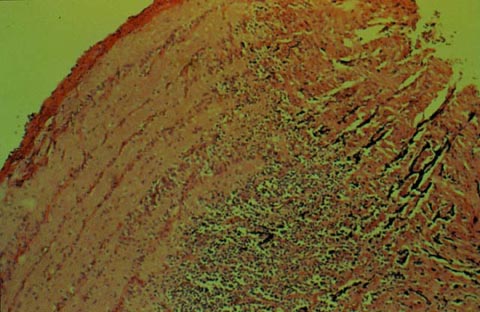

47 year old man with a peripheral retinal lesion found on routine exam

23 year old man with a history of alcohol abuse

20 year old woman with back pain, neck pain, and blurry vision OS

25 year old kickboxer with progressive proptosis